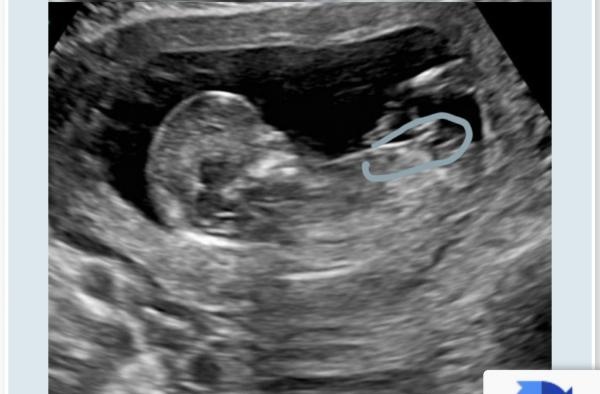

Nub-teorin. Vilket kön?

Hej!Vi gjorde ultraljud i vecka 12+3 och har läst på lite om nub-teorin. Jag tycker att det är lite svårt att veta vad som är nubben så skulle gärna vilja ha lite hjälp att tyda vad ni tror att det är för kön 😀

Ser en tjej-nub, men det är egentligen ingen idé att gissa nuben tidigare än vecka 13+0 eftersom att det fortfarande finns chans att nuben reser sig och visar sig vara en pojke.